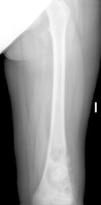

La radiografía del miembro inferior izquierdo mostró una lesión lítica con áreas de esclerosis en diáfisis-metáfisis distal del fémur izquierdo, mal delimitada, de localización medular, que invadía la cortical en el borde externo y con reacción perióstica amorfa (fig. 1). En la RMN femoral se observó una lesión extensa destructiva de la metáfisis distal del fémur izquierdo que afectaba a la totalidad de la cavidad medular y destruía la cortical en la cara externa y posterior, con invasión de los tejidos blandos y extenso despegamiento perióstico compatible con osteosarcoma (fig. 2). La TC torácica y la gammagrafía ósea no mostraron lesiones metastásicas.